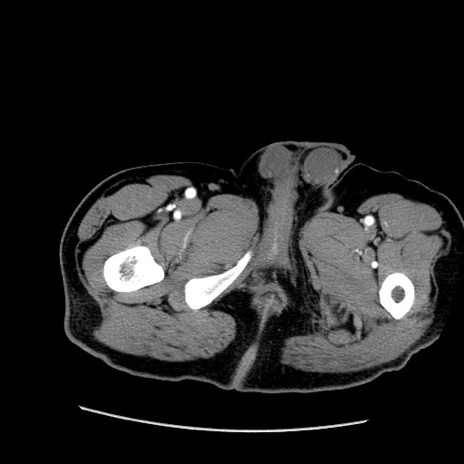

症例22(横断像)

【症例】50歳代男性

【主訴】腹痛

【現病歴】AVMからの被殻出血のため回復期リハ病棟入院中。 本日午後3時頃急に下腹部痛が出現した。

【既往歴】AVM、被殻出血、虫垂炎、高血圧

【身体所見】意識晴明、左半身不全麻痺、会話の理解は良好、36.5°C、腹部:膨隆、全体に板状硬、下腹部正中に圧痛点あり、反跳痛-、筋性防御不明、右下腹部にope scar

【データ】WBC 9400、CRP 0.06